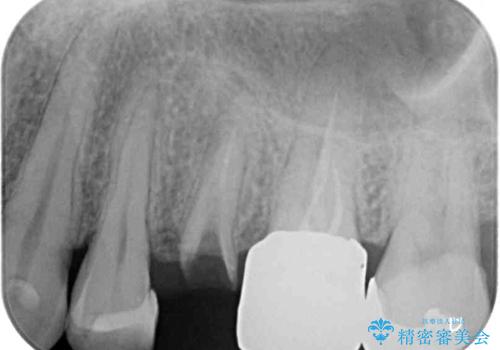

- 頻繁に銀歯が外れてしまうとのことで来院された患者様です。

歯肉の中、深いところまでむし歯が進行しており、歯根を部分矯正で引っ張り出してから補綴治療を行うか、抜歯してインプラント補綴治療を行うか選択することになりました。

海外での勤務があり、部分矯正は困難とのことで、インプラントによる補綴治療を行うこととしました。

より審美的で、より機能的に優れた治療をご希望とのことであったので、ジルコニアカスタムアバットメントを用いたインプラント治療を行うこととしました。